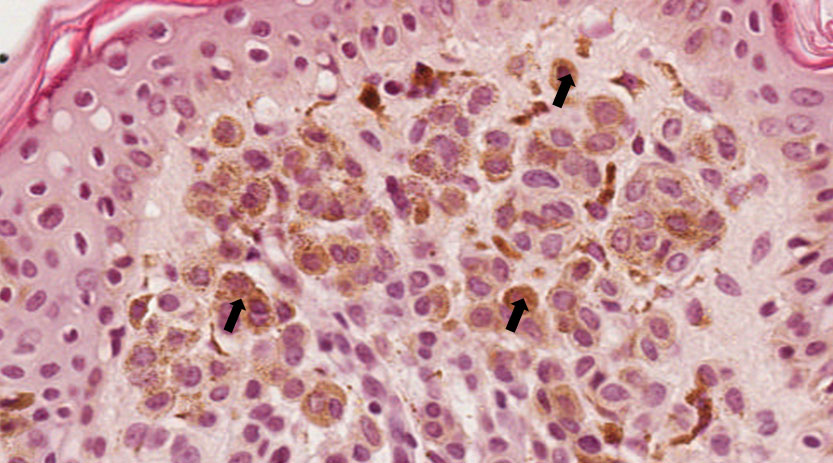

Proliferação benigna de células névicas.

Fragmento de mucosa bucal contendo no tecido epitelial proliferação de células pequenas, escuras e ovoides (células névicas). As células névicas superficiais tendem a estar organizadas em agregados pequenos e arredondados denominados tecas. Com núcleo pequeno e uniforme e uma quantidade moderada de citoplasma eosinófilico com limites celulares indistintos, algumas células névicas apresentam pigmento acastanhado no seu interior. Nesta lâmina, o acúmulo de células névicas está no tecido conjuntivo e no tecido epitelial sendo considerado nevo composto (setas).

Célula melânica, pigmentada na porção superficial da lesão podendo estar presente no tecido epitelial ou no tecido conjuntivo.

Nevo.